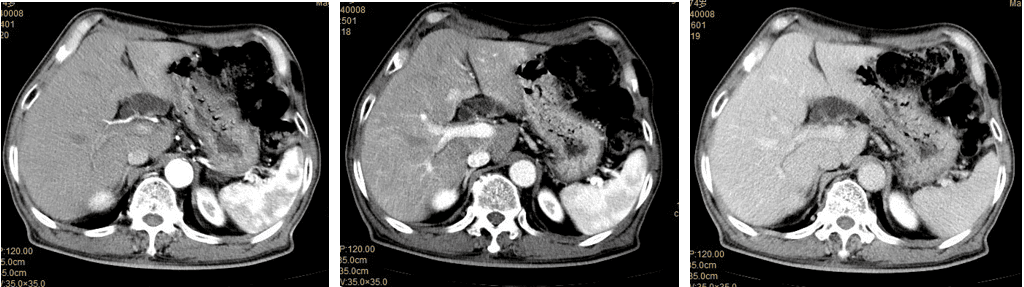

肝脏三期扫描(动脉期、门脉期、延迟期),准确抓住每个时相

3.腹部:肝癌、肝血管瘤、局限性脂肪肝、肝门癌栓、胆管及胆总管病变、胰脾肾占位性病变、胃肠道病变、腹腔肿块及血管病变等。